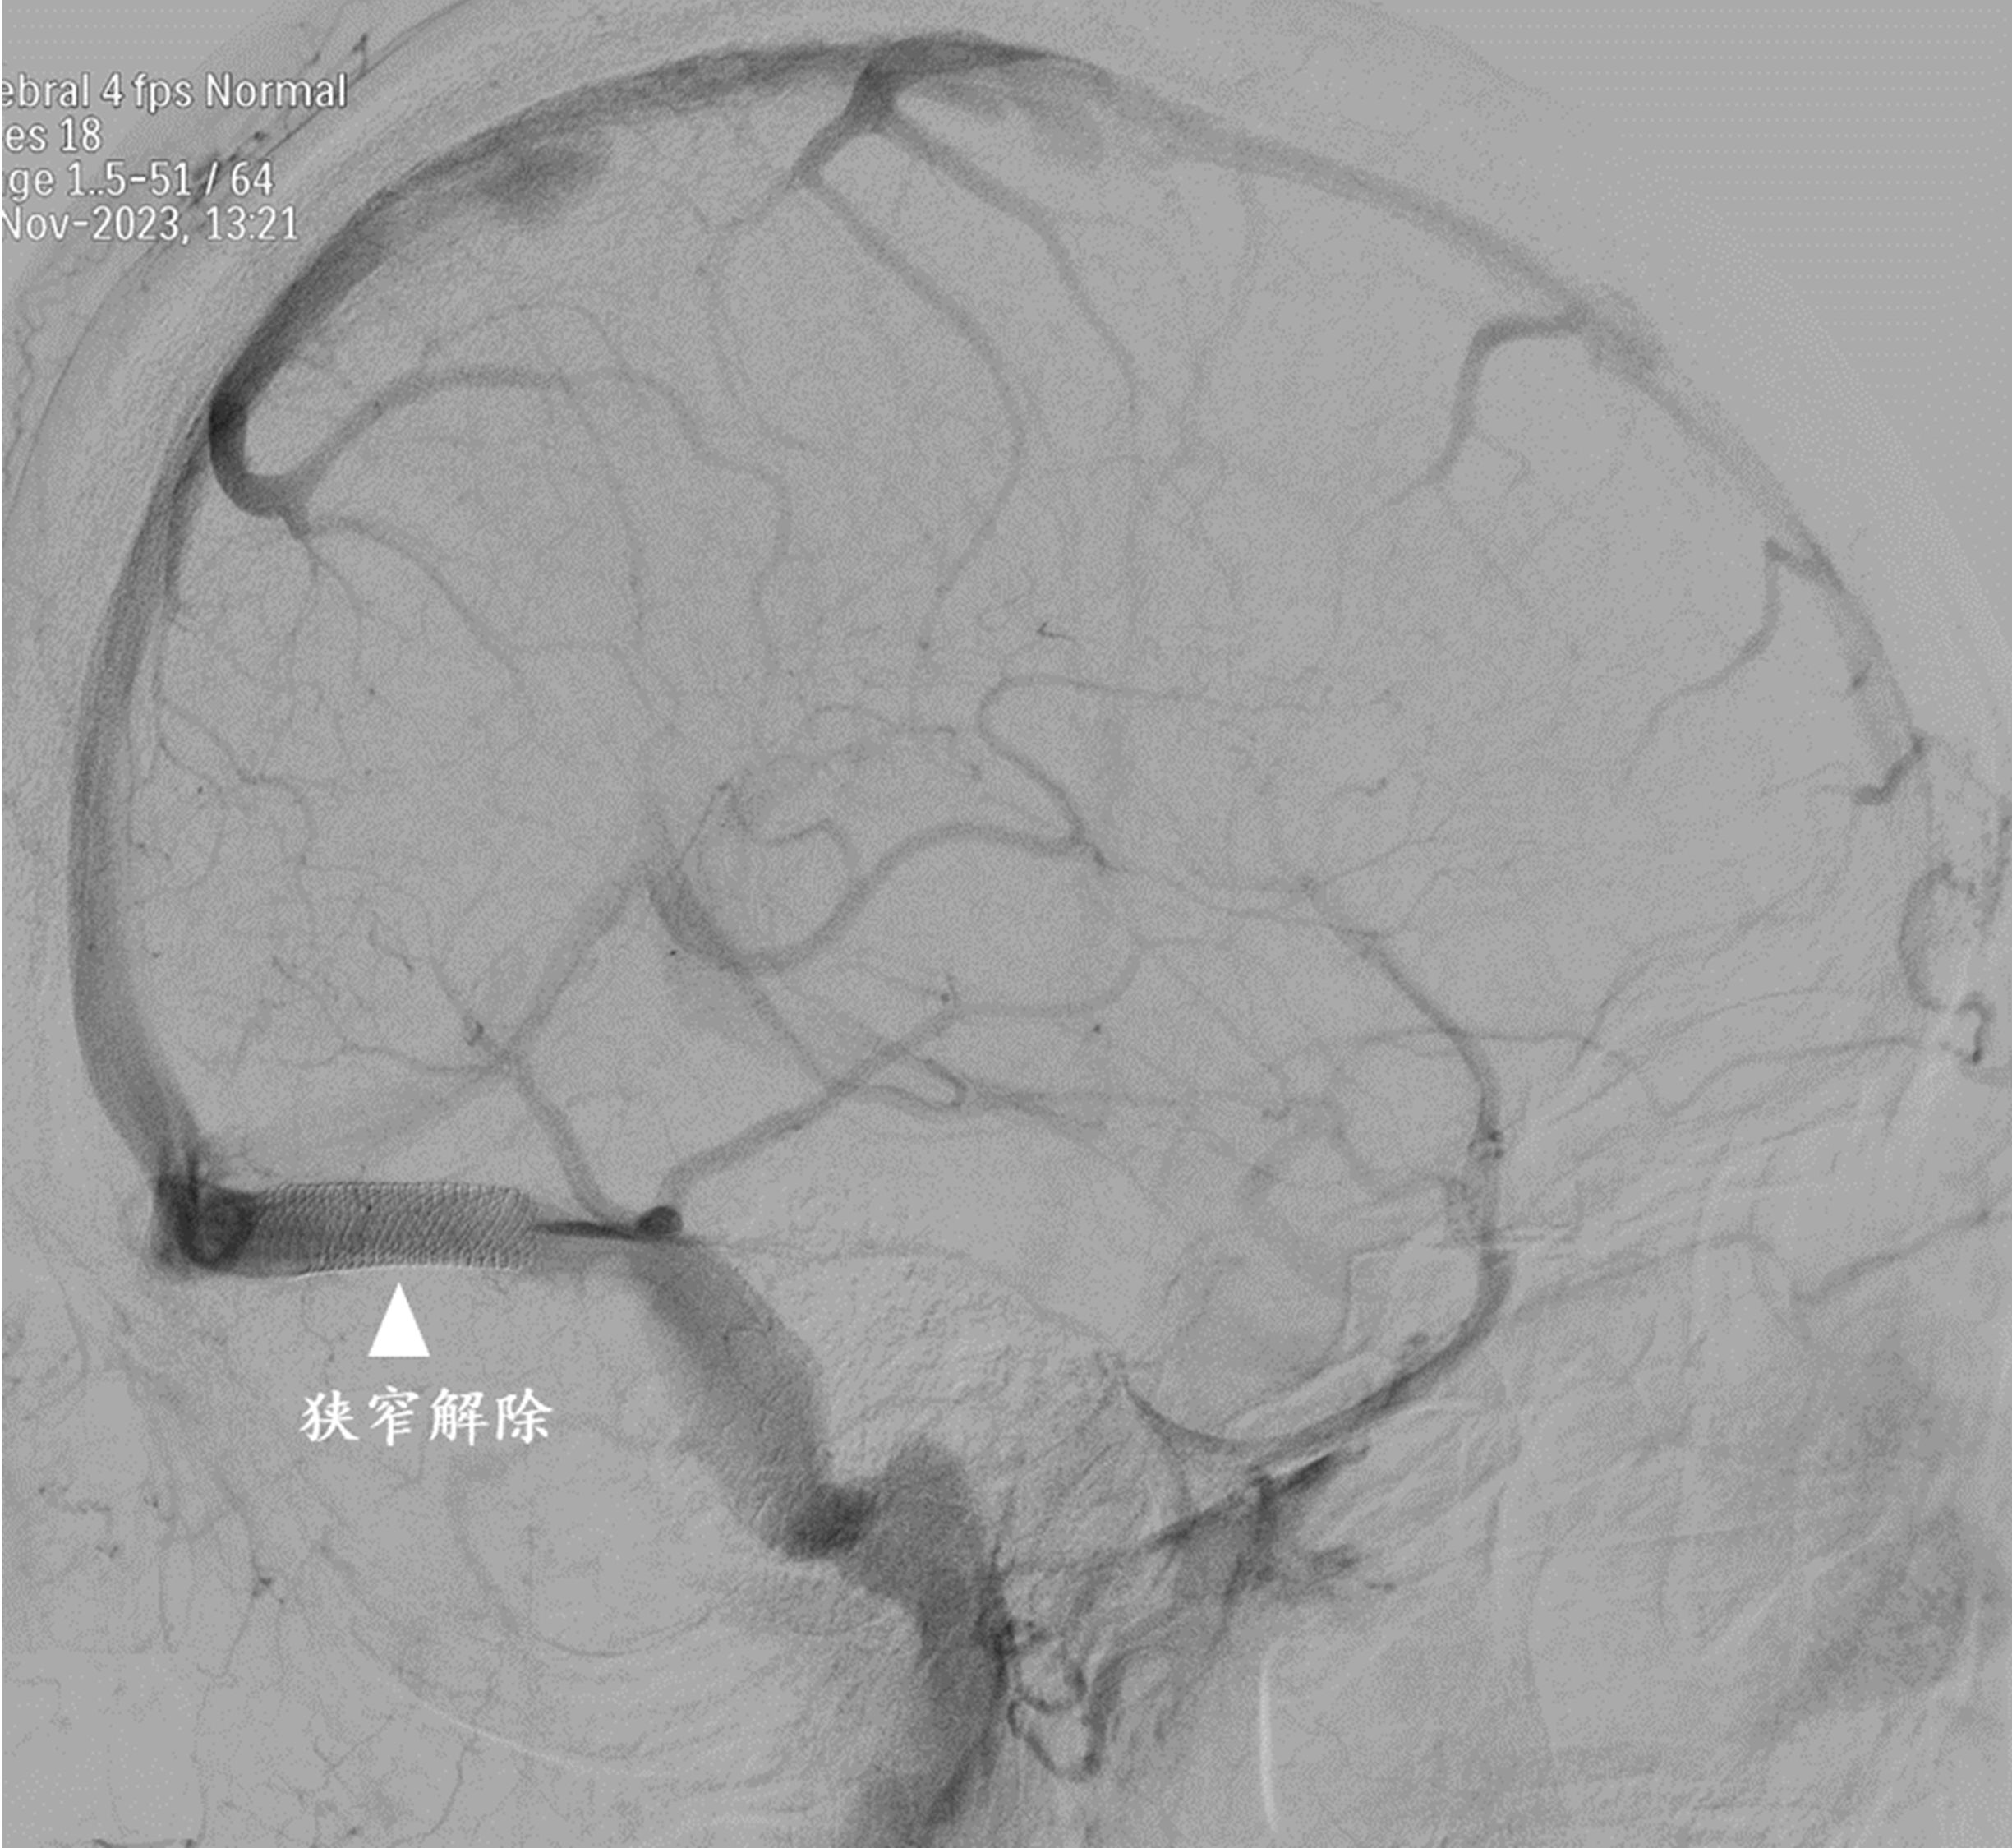

手术非常成功,狭窄的静脉窦被打通。术后,吴女士的头痛症状明显缓解,视物也变得清晰了,左手麻木、无力感消失。

据仁济医院神经外科主任医生潘耀华介绍,颅内静脉窦负责将脑内的血液排出颅腔。如果某个优势静脉窦发生狭窄,阻碍了血液的正常流动,就可能引起颅内压升高,从而导致一系列症状,如头痛、视物模糊、视力下降甚至失明、搏动性耳鸣,甚至出现明显的肢体感觉活动障碍。脑血管造影是诊断该疾病的金标准,能够同时测定静脉窦狭窄两端的压力差,有助于明确诊断,并指导治疗和判断预后。对于静脉窦严重狭窄且狭窄两端存在明显压力差的患者,血管内微创重建静脉窦是一种安全可行的治疗方法。